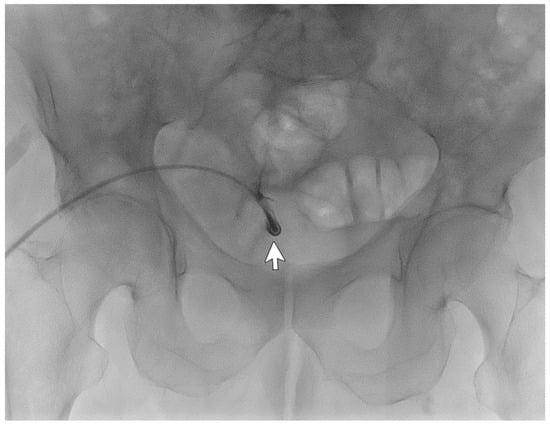

A 77-year-old male patient with ESKD secondary to diabetic kidney disease underwent placement of a “Vicenza Short”peritoneal catheter by open surgical dissection under local anesthesia. Peritoneal dialysis was started after two weeks, but poor drainage performance with a large residual volume was immediately observed. An abdominal X-ray documented coprostasis and the right location of the peritoneal catheter tip in the pelvis. The patient tried different laxatives and enemas without improvement in the outflow performance of the catheter. The patient underwent catheterography that demonstrated regular inflow but impeded outflow function. The catheter appeared to be stuck on the postero-lateral side of the iliac right region (Figure 2), and wire-guided manipulations failed to move it from its original position. The patient reported mild pain after the procedure that was easily relieved with oral acetaminophen.

The CT abdomen scans disclosed adipose tissue entrapping the peritoneal catheter near its insertion in the abdominal cavity and the tip being right before the bladder wall. Considering the patient’s comorbidities, he was not eligible for videolaparoscopic rescue and thus was subjected to peritoneal catheter removal and replacement with a longer one (Vicenza) through a mini-laparotomy surgery. This catheter showed better hydraulic function and allowed the patient to finally perform adequate peritoneal dialysis.

In this case, catheterography failed to diagnose the cause of malfunctioning, and the CT scan lateral film aided it.

Figure 2. Catheterography showing the peritoneal catheter with the tip (Life 14 01475 i002) ending in the right iliac region.